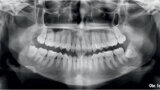

Distalizace horních molárů pomocí alignerů a cyklických sil